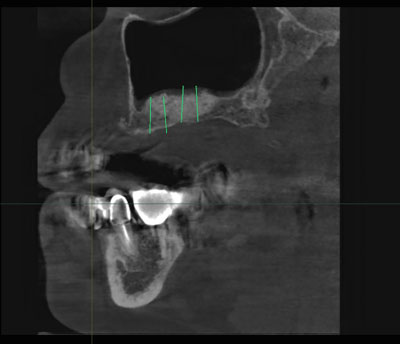

Также при планировании имплантации после операции синус-лифтинг, хирург зачастую сталкивается с необходимостью получать четкие данные о плотности аутотрансплантата или остеопластического материала с целью подготовки к следующему оперативному этапу. В таких случаях 3D-технологии помогают произвести волюмометрическую оценку синус-лифтинга в отдаленные сроки. Применить специальный планировщик дентальной имплантации в программном обеспечении Ez3D-i. При виртуальной установке имплантата посредством различных инструментов, возможно правильно наметить оси, измерить ширину альвеолярного отростка, расстояния от вершины альвеолярного гребня до дна верхнечелюстных пазух. С помощью специально встроенной опции производится выбор системы - производителя дентальных имплантатов, длины и диаметра имплантата, цветовые показатели мультимедийного ролика. После того как программа спозиционировала имплантат, хирург может моделировать его ангуляцию, инклинацию и погружение, учитывая все анатомические факторы риска. Также существуют функции "Удалить или Скрыть" имплантат, тогда возможно настроить по-другому планировщик и выбрать имплантат другой длины и диаметра или иной марки производителя (Рис.2).

Рис.2 Дентальная объемная томограмма и ортопантомограмма. Планировщик программного обеспечения Ez3D-i и EzDent-i. Виртуальная инсталляция дентальных имплантатов в проекции отсутствующих 15,16,17 зубов после аугментации альвеолярного отростка посредством операции открытый синус-лифтинг